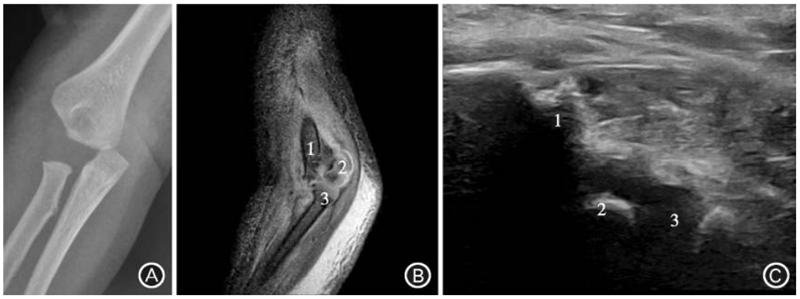

图1 患者男,1岁,右肘关节摔伤,诊断为肱骨远端骨骺分离骨折。A.正位X线片示肱桡关节不匹配,远端尺偏,类似肘关节脱位;B.矢状位MRI示肱骨远端肱桡关系正常,桡骨头正对肱骨小头,肱骨远端骨骺滑脱不伴有干骺端骨折块;C.纵切面超声表现与 MRI一致,肱骨远端肱桡关系正常,桡骨头正对肱骨小头,肱骨远端骨骺滑脱。注:1为肱骨,2为肱骨小头,3为桡骨头